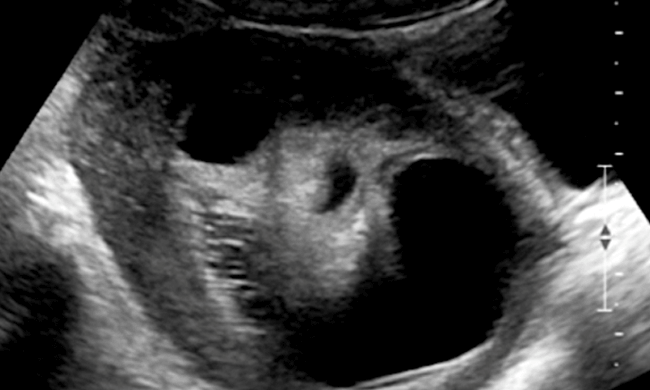

“组织囊肿”或皮样囊肿(或良性成熟囊性畸胎瘤)通常含有油性组织和毛发。皮样囊肿的形成是因为卵巢中的细胞可以发育成任何类型的身体组织。因此,这些囊肿通常含有皮肤、脂肪、骨骼和软骨。10%的情况下,皮样囊肿会发生在双侧卵巢。